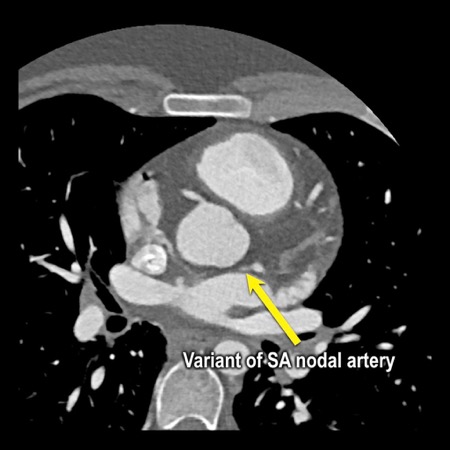

stenosis in the proximal LAD caused by a non-calcified plaque. - Variant of

sinoatrial (SA) nodal artery. The artery usually arises from the RCA as a second

branch after the conus artery, however in this case it arises from the LCX,

courses behind the aorta, anastomosing with the right atrium and with a small

branch supplies the SA-node of the heart. - Thrombus in the

B: The so-called “spider-view” (LAO caudal) of the heart with a 70% stenosis in the proximal LAD. Note the presence of SA nodal artery arising from the proximal LCX and coursing to posterior direction.